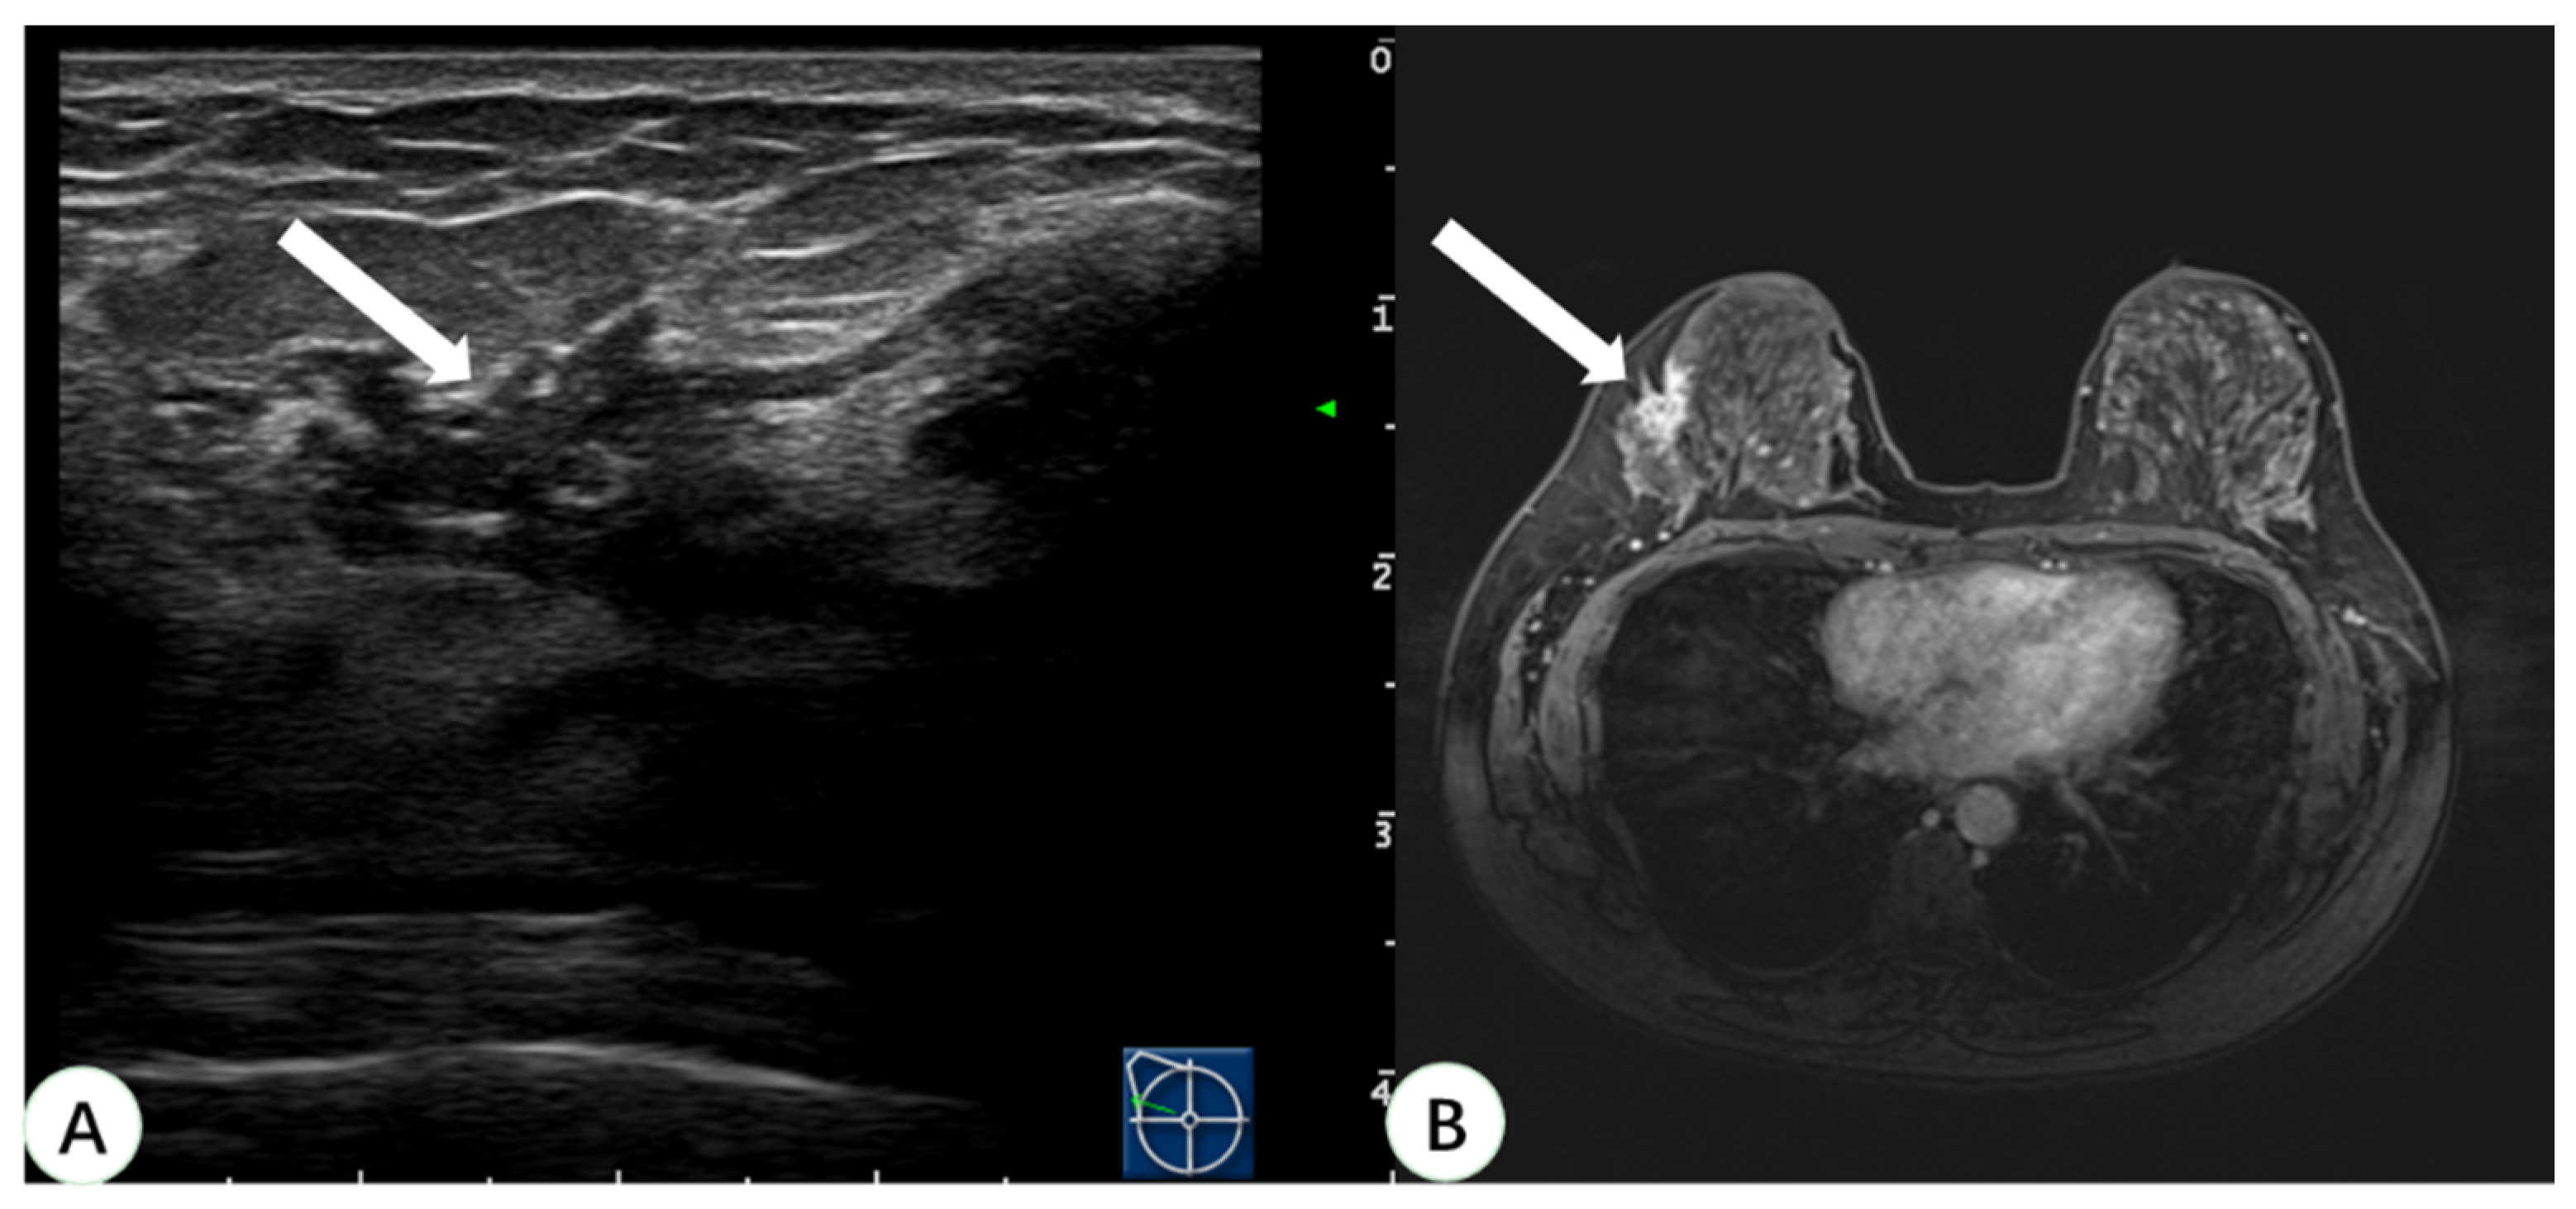

In the present study, 93.9% of the 33 lesions detected on MRI but negative on second-look US were NME lesions. An NME lesion detected on MRI usually presents as a localized hypoechoic area or fuzzy area with a structural disorder or catheter abnormality on US [20]. It is difficult to confirm the diagnosis with US because there is no obvious tumor entity or mass effect. Virtual navigation can synchronize fusion US and MRI images and can display the suspicious lesions detected on MRI in real-time US, which can then be positioned or sampled under US guidance (Figure 5). Studies by Uematsu and Watanabe et al. [8,13] have shown that virtual navigation can improve the US detection rate and biopsy rate of breast lesions found on MRI only.

Figure 5.

A 44-year-old woman with dense breast tissue underwent virtual navigation: (A) Real-time US with virtual navigation revealed the corresponding lesion (arrow) in the right breast at the 10-o’clock position 5 cm from the nipple, which underwent ultrasound-guided biopsy; (B) CE-MRI showed a non-mass enhanced lesion (arrow) in the upper outer right breast, undetected on second-look US. Pathology obtained by ultrasound-guided biopsy with virtual navigation demonstrated sclerosing adenopathy with intraductal papilloma formation. US = ultrasound; CE-MRI = contrast-enhanced magnetic resonance imaging.